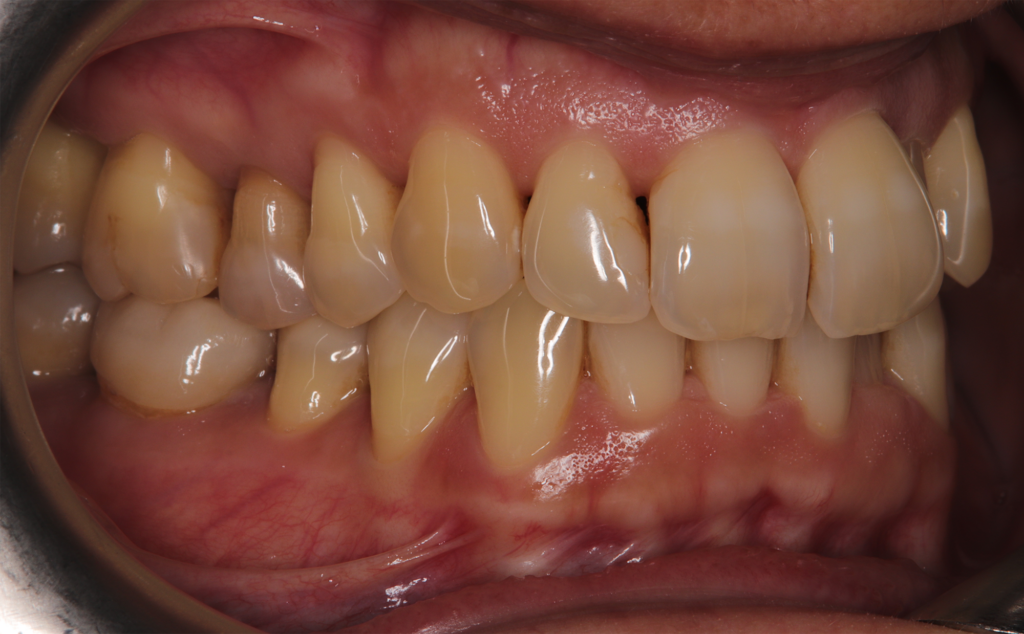

The patient, having completed a periodontal treatment phase, presented with significant aesthetic and functional concerns due to moderate crowding in both arches and a pronounced anterior crossbite. Clinical examination confirmed the need for comprehensive realignment, particularly in the anterior region. Although the patient had a history of periodontal issues, radiographic evaluation showed no signs of active disease. Based on these findings, the treatment plan was designed to carefully modulate orthodontic forces to protect the occlusion and surrounding tissues while addressing the misalignment.

To correct the misalignment and anterior crossbite without compromising tissue stability, a slower orthodontic treatment plan was devised using the Spark Advanced clear aligner system. The initial phase involved 36 aligners designed to gently expand and realign the dental arches, limiting the rate of tooth movement. Strategic interproximal reduction (IPR) was performed in the anterosuperior region (between teeth #21 and #11) to create the necessary space for proper alignment while avoiding excessive loading on the tissues.

To refine the results and enhance aesthetics, a second phase incorporating an additional 17 aligners was introduced. During this refinement stage, careful IPR in the lower arch helped harmonize the midline and achieve a balanced occlusion. Once satisfactory alignment was reached, provisional composite restorations were placed on the upper lateral incisors to aesthetically close any interproximal gaps.

A crucial aspect of the treatment was reducing the speed of tooth movement by 50%. This approach allowed a gradual application of orthodontic forces, giving the occlusion and tissues ample time to stabilize following the periodontal phase while effectively addressing the crowding and anterior crossbite.

At the conclusion of the treatment, the patient achieved excellent dental alignment and a stable occlusal relationship, particularly in the anterior region. Radiographs and clinical assessments confirmed that there was no further bone loss and that previous improvements were maintained. The aesthetic enhancement from the composite restorations further contributed to the overall success of the treatment.